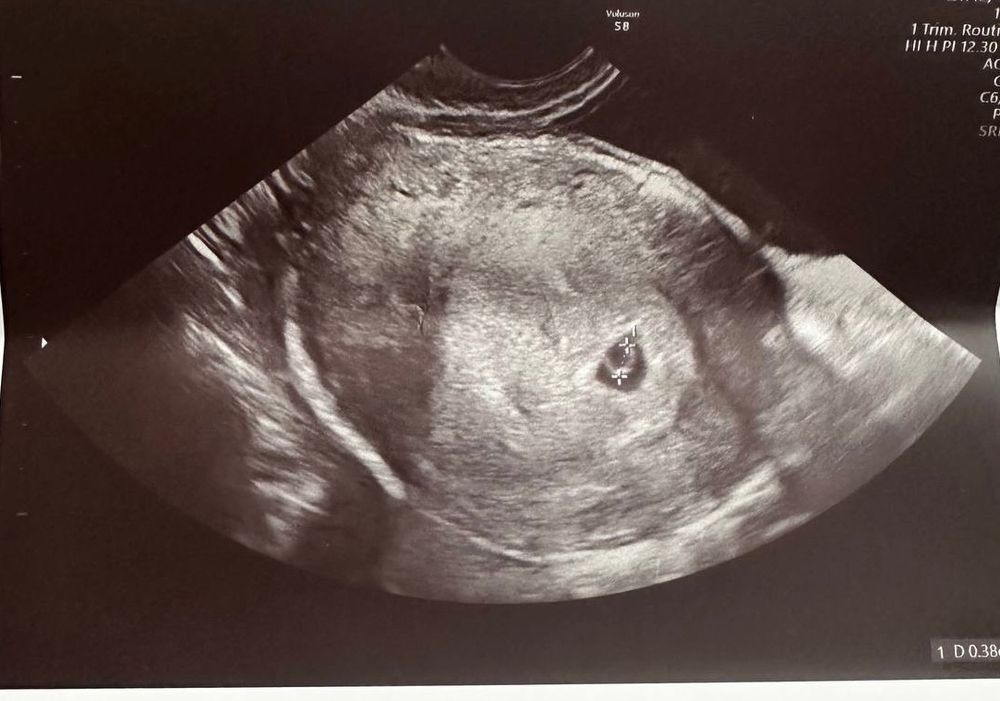

Девочки, всем привет! Не выдержала я и сходила на узи раньше положенного, на 5,5 акушерской неделе. Ре толком ничего не сказала, только что есть плотное яйцо и желточный мешочек, что оно соответствует сроку, а эмбриончика не нашли(( Я так расстроилась. Хгч 25.09 был 2322, 29.09 8222, не мало ли это? Мне кажется не удвоился как нужно. Прогестерон 86,5.